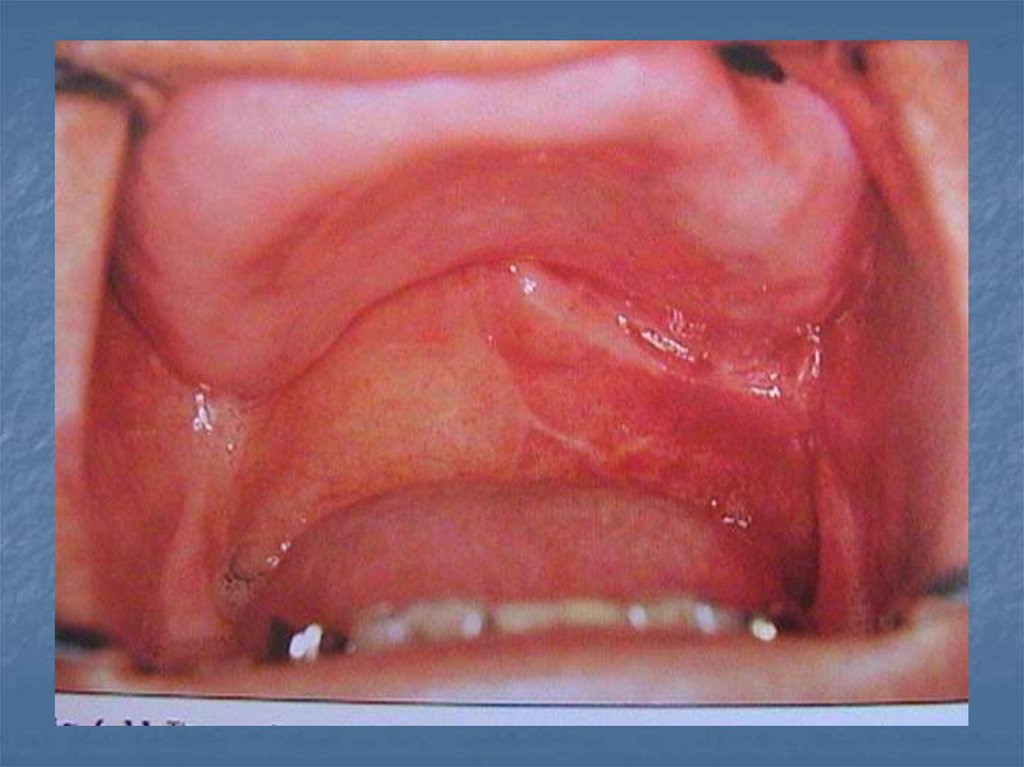

52. İmmediat obtüratörler

Ameliyattan önce ölçü alınır. Ameliyat

edilecek bölge model üzerinde tahmini

olarak kazınır. Protez hazırlanır. Ameliyatı

takib eden dakikalarda takılır kullanma

süresi 8-12 haftadır.